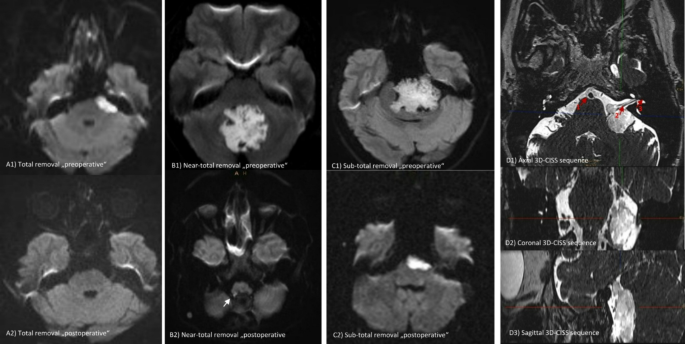

The extent of removal was assessed based on first available postoperative MR imaging, with special emphasis on diffusion-weighted imaging to accurately identify residual epidermoid tissue. Here, early DWI scans were consistently utilized as the follow-up imaging modality for all cases, with a median time from surgery to the first MRI in our cohort of 3 months (Interquartile Range “IQR”: 3–4 months). The extent of removal was classified into three categories: “total,” “near-total,” and “subtotal” removal. Specifically, “total removal” was defined as the complete absence of diffusion-restricted remnants on MRI. “Near-total removal” was classified as achieving a resection of ≥ 98–99% of the lesion, while any residual lesion beyond this threshold was considered “subtotal removal” (Fig. 1). Furthermore, the use of endoscope war reported in the result section, the decision to use endoscopy was made at the discretion of the surgeon, based on mainly the intraoperative finding including nonetheless, factors like blind spot visualization, tumor adherence, anatomical constraints and facilitate safer dissection around critical neurovascular structures. Long-term radiological follow-up was conducted, with Kaplan–Meier recurrence-free survival curves generated for the total removal group, and regrowth-free periods assessed for the near-total and subtotal removal groups. Concerning the predictors of lesion regrowth, adhesion severity was determined through a detailed review of operative reports, as well as preoperative and postoperative MRI scans, categorizing lesions as either less adhesive or more adhesive. Additionally, postoperative clinical assessments and one-year follow-up examinations were obtained for each patient to establish longitudinal evaluation of neurological condition. Functional status was appraised using the Modified Rankin Scale (mRS) (preoperatively, at discharge and at subsequent follow-ups).

Preoperative and postoperative DWI MRI studies illustrating the classification of the extent of resection: (A) Total removal, (B) Near-total removal, and (C) Subtotal removal. (D) 3D-CISS sequence showing neurovascular structures surrounding an epidermoid tumor in the cerebellopontine angle (CPA). Specific structures labeled in (D1):1 – Basilar artery, 2 – Cranial nerves VII and VIII, 3 – Internal acoustic meatus.